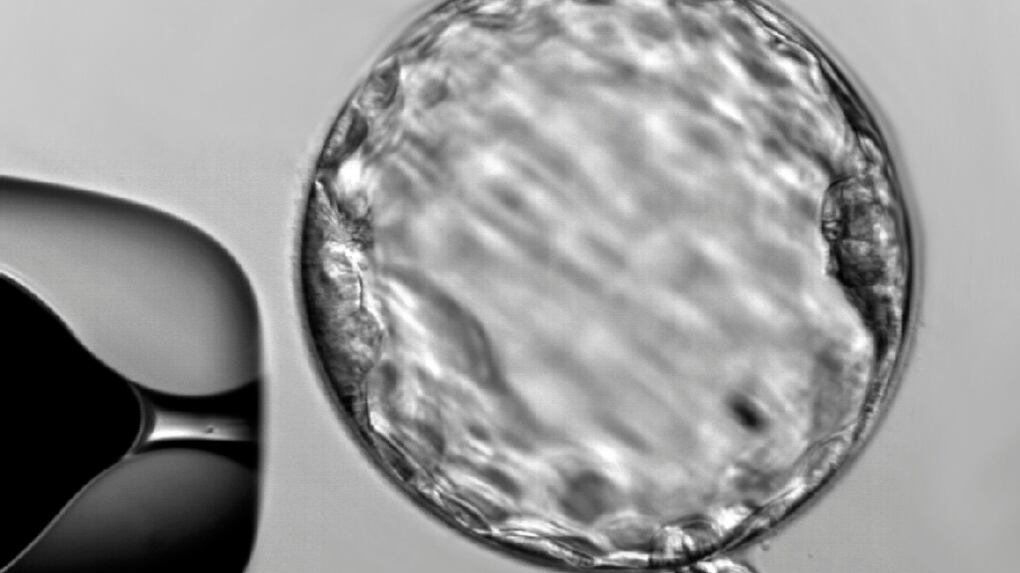

Genome editing reveals key gene for human embryo growth